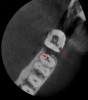

Finally, CBCT can help the clinician diagnose the cause of endodontic failures, especially when untreated canal anatomy is present (Figure 11).It can aid in determining whether a nonsurgical or surgical approach is needed. In addition, CBCT imaging is invaluable in surgical treatment planning, particularly if the roots of the tooth approach the maxillary sinus, mandibular canal, or mental foramen. For diagnosing root fractures or cracks, both horizontal and vertical, in this author's experience, root fractures can be seen on most CBCT scans if the crack has separated by at least 75 microns and most vertical root fractures are diagnosed by a narrow pattern of periradicular bone loss along the lateral aspect of a root.

Fig 11. 3D CBCT image of an untreated MB2 canal in tooth No. 14.

Figure 11